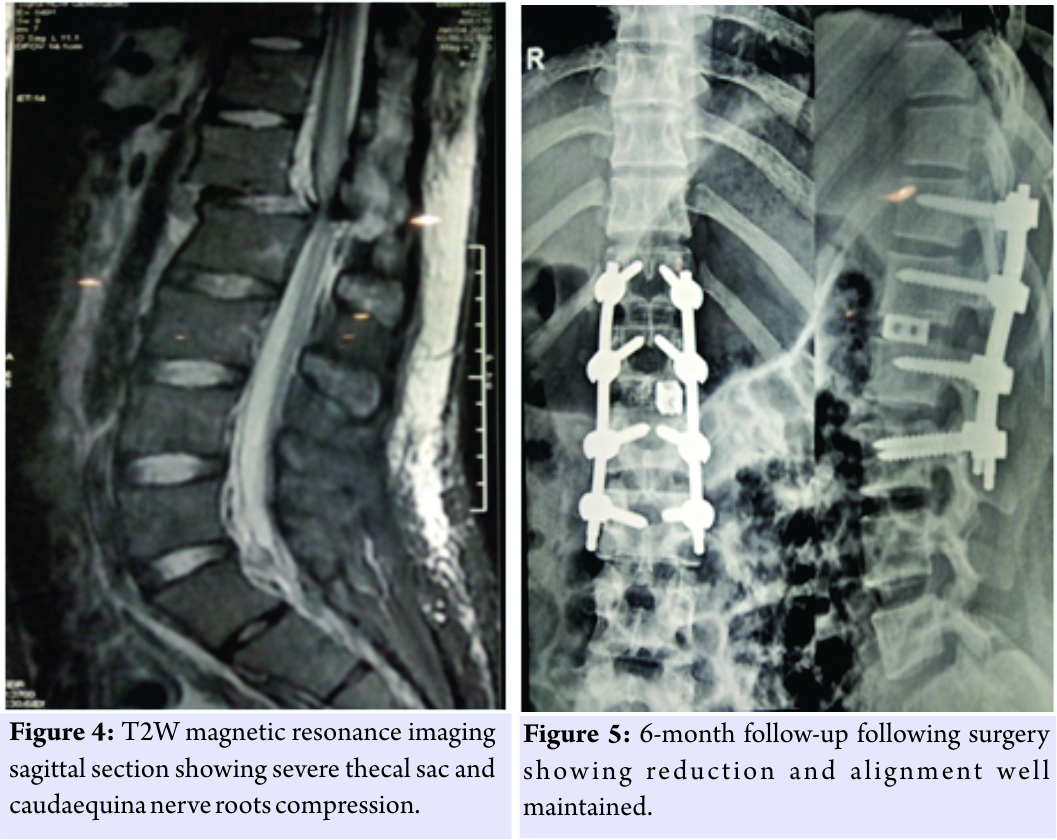

On clinical examination, he had a distended abdomen, pitting edema over the left lumbar region and left thigh, with weak (Grade 2) quadriceps along with reduced sensations over the anterior thigh. His knee reflex was absent on the left side, and hip and knee movements were painful. Left femoral pulse was feeble, and the patient was unable to perform a straight leg raise. Movements of opposite hip and knee were full and pain-free with an intact neurovascular status. Investigations had revealed that the total counts, renal parameters, and liver enzymes were elevated with a hemoglobin of 8 g/dl. Ultrasound abdomen revealed a large mass in the left hypochondrium and iliac region which was confirmed as a retroperitoneal organizing hematoma contiguous with the left psoas and iliacus without any active bleeding in the abdomen. The massive dimensions of the lesion were 22 cm × 16 cm × 14 cm (Fig. 1 and 2). The case was managed conservatively with cessation of anticoagulants, limb elevation and bed rest and had made complete neurological recovery at subsequent follow-up at 1 month.

Cadaveric studies have demonstrated that while the iliacus muscle can expand to its maximum limit of 150 ml, the psoas has a much higher capacity to tumefy [6]. These findings are only suggestive of the significant amount of blood that these muscles can hold even before the patient is symptomatic. A review of the literature demonstrates that there has been no consensus regarding the treatment of choice. Aggressive decompression has been propounded to forestall impending neurological deficits with inflated intramuscular tension [7, 8]. As with our case, conservative management can be effective provided the patient is hemodynamically stable and is monitored regularly [9]. Modification or cessation of anticoagulant therapy, correction of the hemodynamic state with volume resuscitation stabilization by adequate transfusion and supportive measures form the pillars of medical treatment. It is to be noted that a progressive hematoma with evidence of neurological worsening decrees an urgent decompression and drainage [10].